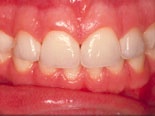

Fyra skalfasader före och efter behandling. De två understa bilderna visar en gipsmodell av patienten, i vy från gommen och tuggytorna på framtänderna. Till höger kan du se de tunna keramiska fasaderna.